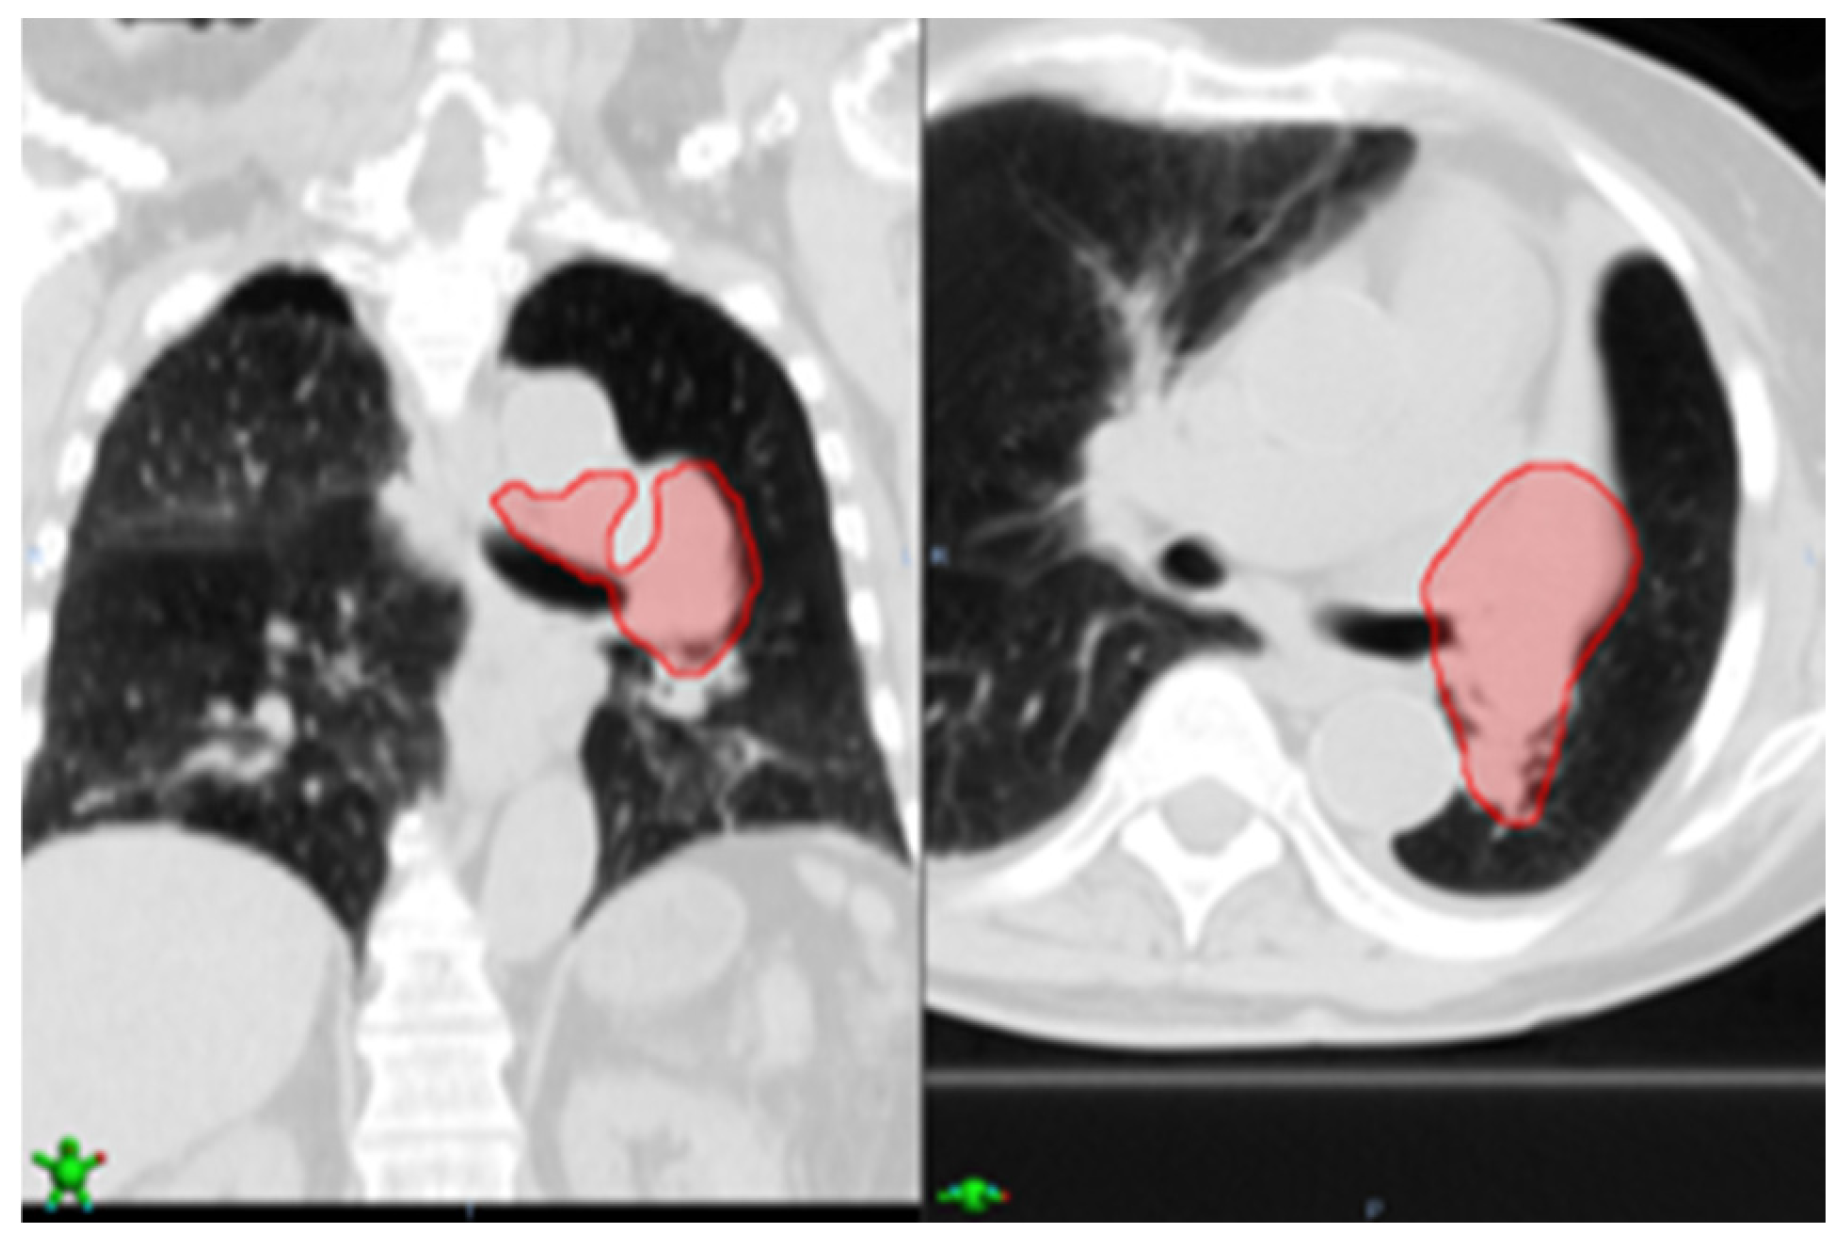

As for case 10 (Figure 6), the nodule detection method found an FP nodule in the right upper lobe. According to the EHR report, the tumor was in the left upper lobe, thus the FP was averted. However, case 10, particularly, is highly advanced stage 4 and thus very challenging. As seen in Figure 6, the tumor spread a lot and involved a large area of lymph nodes. Because currently our model is not trained on these challenging cases, it failed to detect the tumor.

Figure 6. Case 10, our approach averted a false positive in the right upper lobe; however, due to highly advanced stage 4 cancer, the nodule detection failed to detect the advanced tumor shown in the red shade (left coronal view, right axial view).